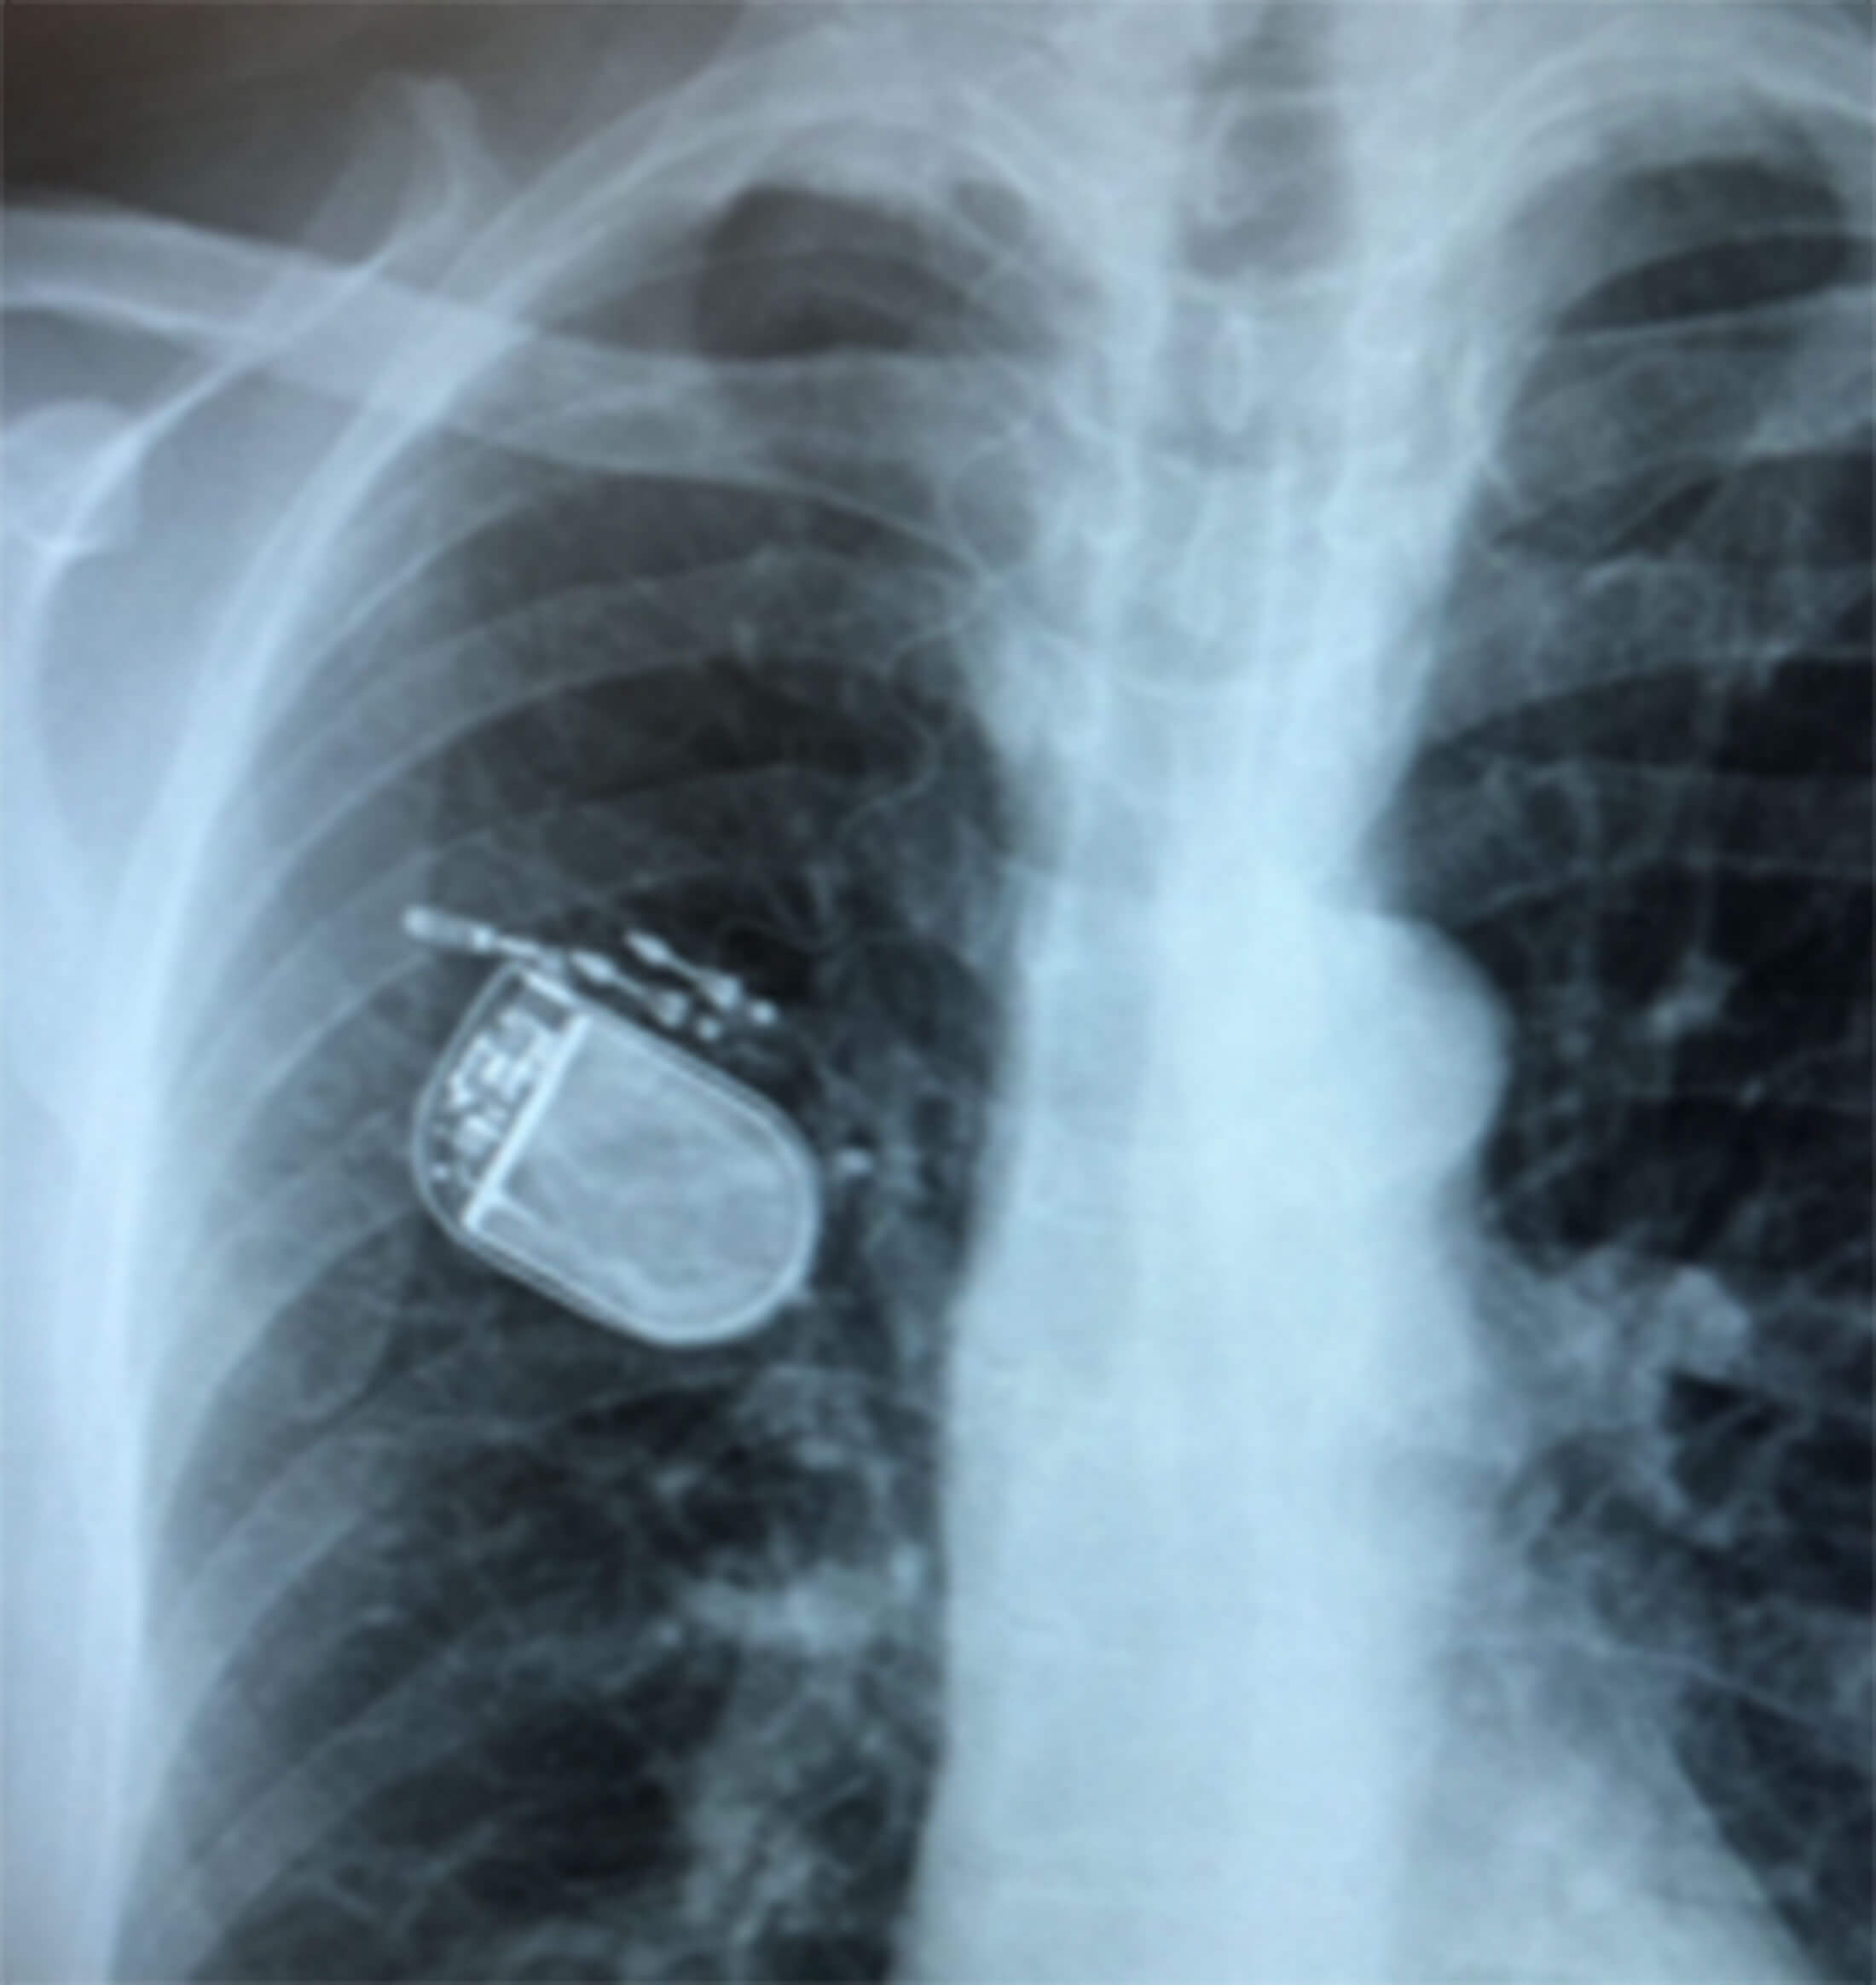

- An impulse generator placed subcutaneously over the pectoralis major muscle on the right chest wall through an incision made 5cm below the right clavicle and 3cm lateral to the lateral border of the sternum on the right side (Figures 3a-b).

Figure 3b. Postop chest X-Ray showing the pulse generator in situ.